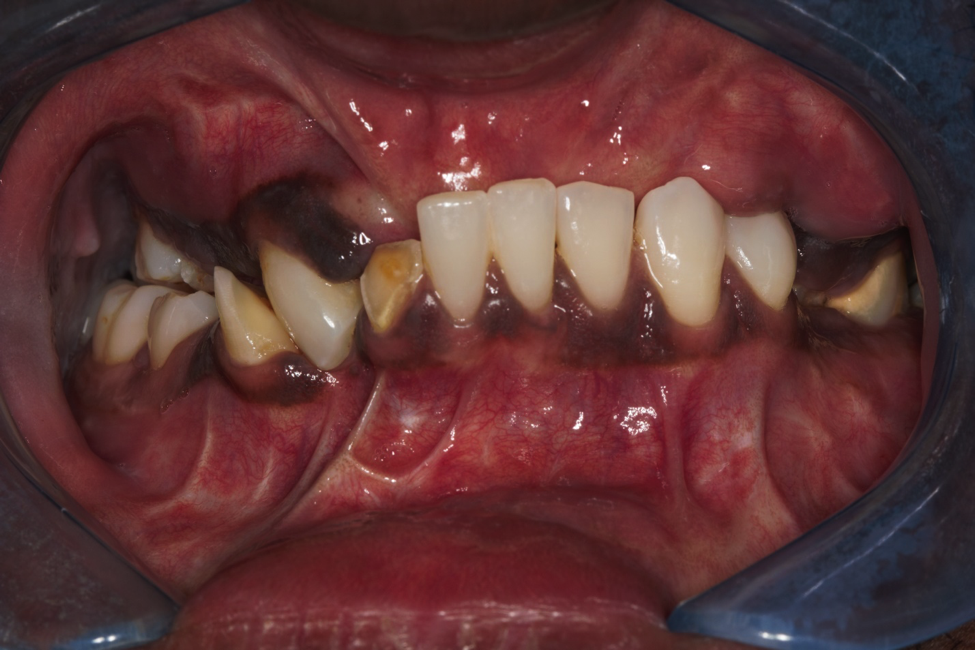

This patient came to us because he suffered from major trauma to his Jaw. His entire jaw and face was reconstructed and you can see how this affected his teeth. We extracted all his teeth and placed several implants in his jaws. Four implants in the top jaw and four implants in the bottom jaw. We then made him a combination of fixed bridges in ceramic and implant dentures that were reinforced in metal to restore his bite and his smile.